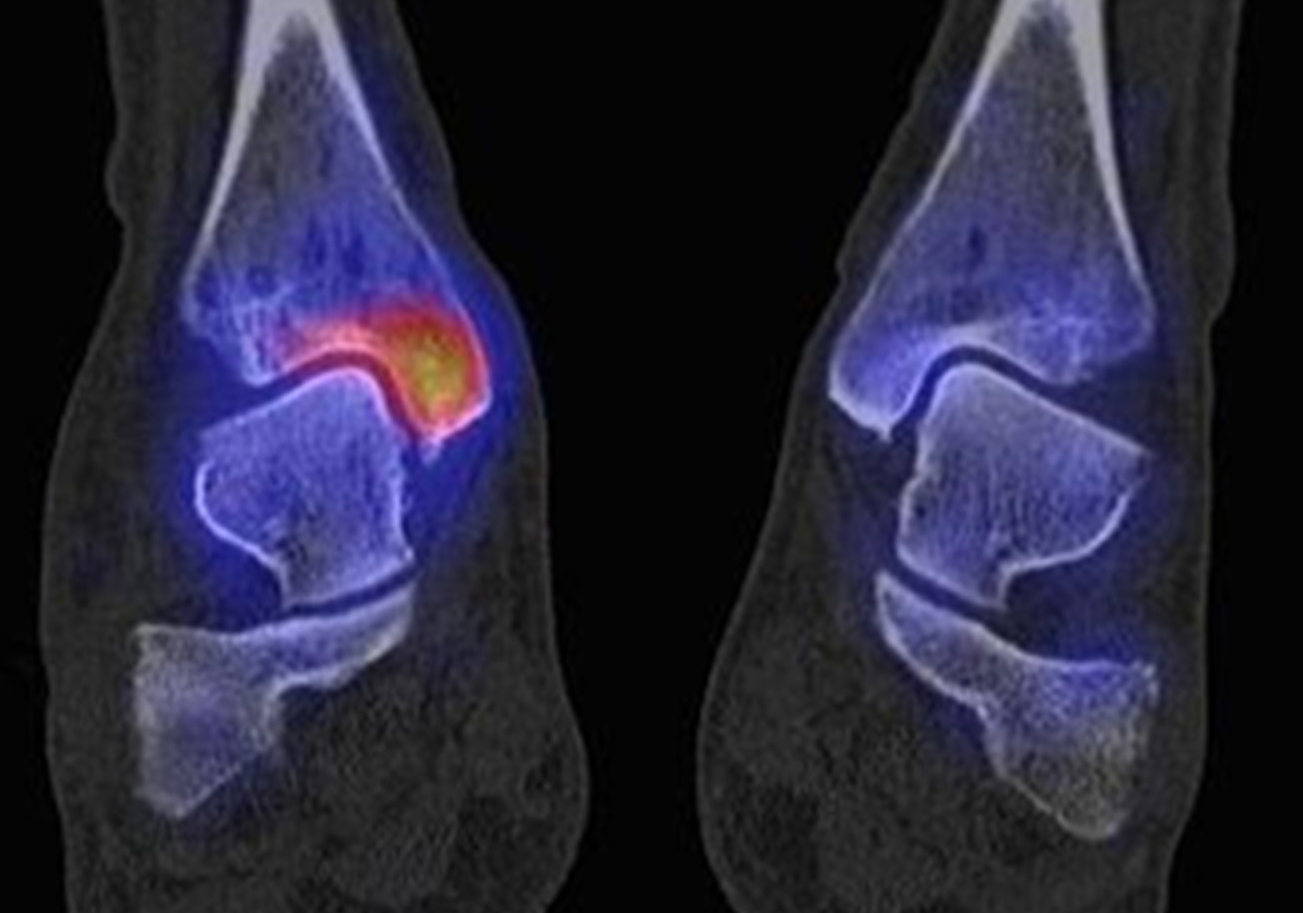

Abbildung 1.8.a und b: Akute Arthritis bei bekannter Gicht in beiden OSG: links die Früh-/Weichteilphase; rechts die Mineralisations­phase. Deutliche, entzündlich bedingte Mehranreicherungen in der Früh-/Weichteilphase. In der Mineralisation­sphase erkennt man die entzündliche Mitreaktion der subchondralen Gelenkabschnitte.

Abbildung 1.8.c - e: Akute Arthritis in beiden OSG, rechts > links. Im SPECT/CT erkennt man die Mitreaktion der subchondralen Gelenkabschnitte. Die Arthritis ist so akut, dass (noch) keine ossären morphologischen Veränderungen im CT abgrenzbar sind.